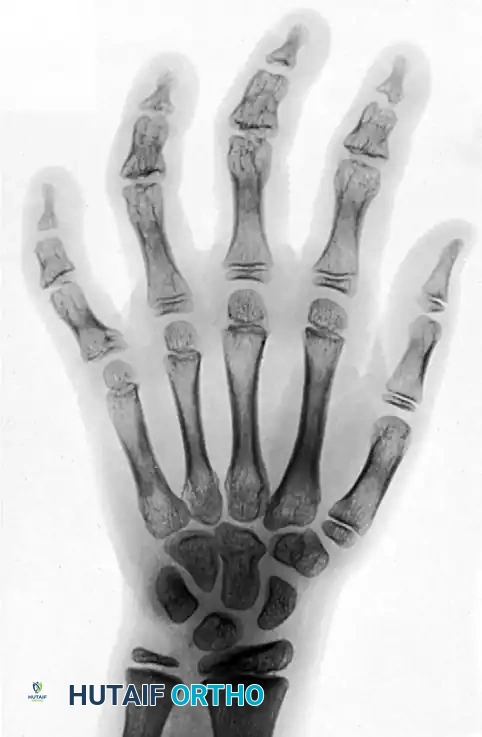

Clinical Radiograph: Deformities of the fingers in a 12-year-old girl caused by severe frostbite incurred at age 2 years. Note the profound destruction of the epiphyses of the middle and distal phalanges across all fingers, and the severe angular deformity of the epiphysis of the proximal phalanx of the little finger. The osseous changes demonstrate the classic delayed manifestation of cold-induced physeal arrest.